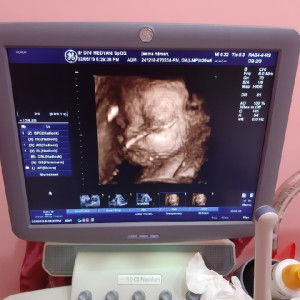

usia kandungan 7 bln